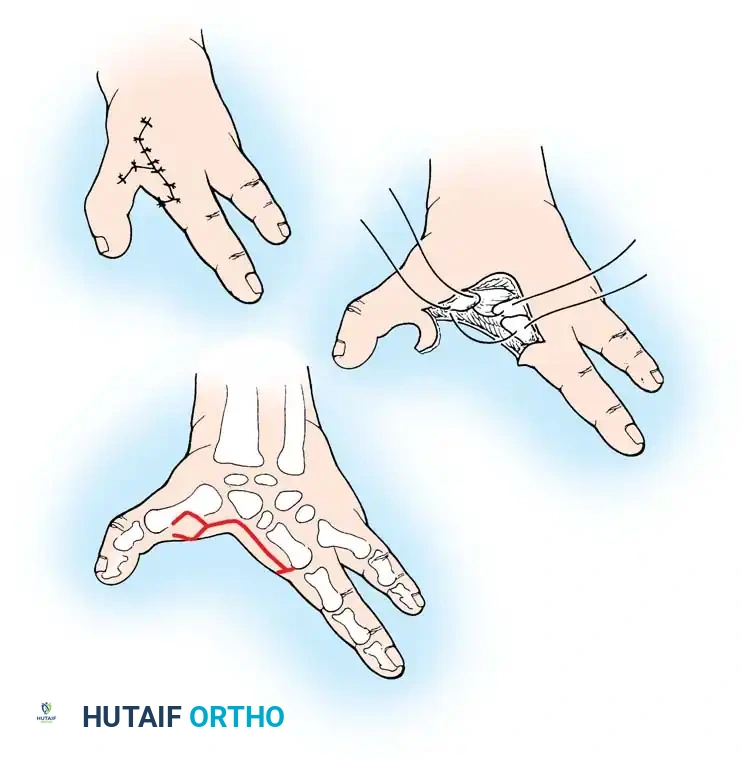

Prosthetic Protocol by Age:

1. 3 to 6 Months (Sit to Fit): A passive plastic mitten prosthesis is introduced once the child achieves independent sitting balance. This provides stability during sitting and assists in pulling to a stand.

2. 12 to 18 Months: The passive mitten is exchanged for an actively opened, plastisol-covered split hook. A Child Amputee Prosthetic Program (CAPP) terminal device may be substituted. Training with the functional device begins immediately.

3. 2 to 4 Years: A myoelectrical prosthesis may be considered. Studies have shown these to be highly useful and appropriate for preschool-aged children, offering superior cosmesis and intuitive grip control.

4. 3 Years and Older: For above-elbow amputations, dual-terminal devices and articulated elbow controls (friction elbows) are introduced.

Surgical Warning: Prosthetic management for midcarpal amputations remains controversial. The long, below-elbow stump is exceptionally useful for stabilizing objects and bimanual function because it retains native sensibility. Sacrificing terminal sensibility for a cosmetic artificial hand must be carefully weighed against the functional loss.